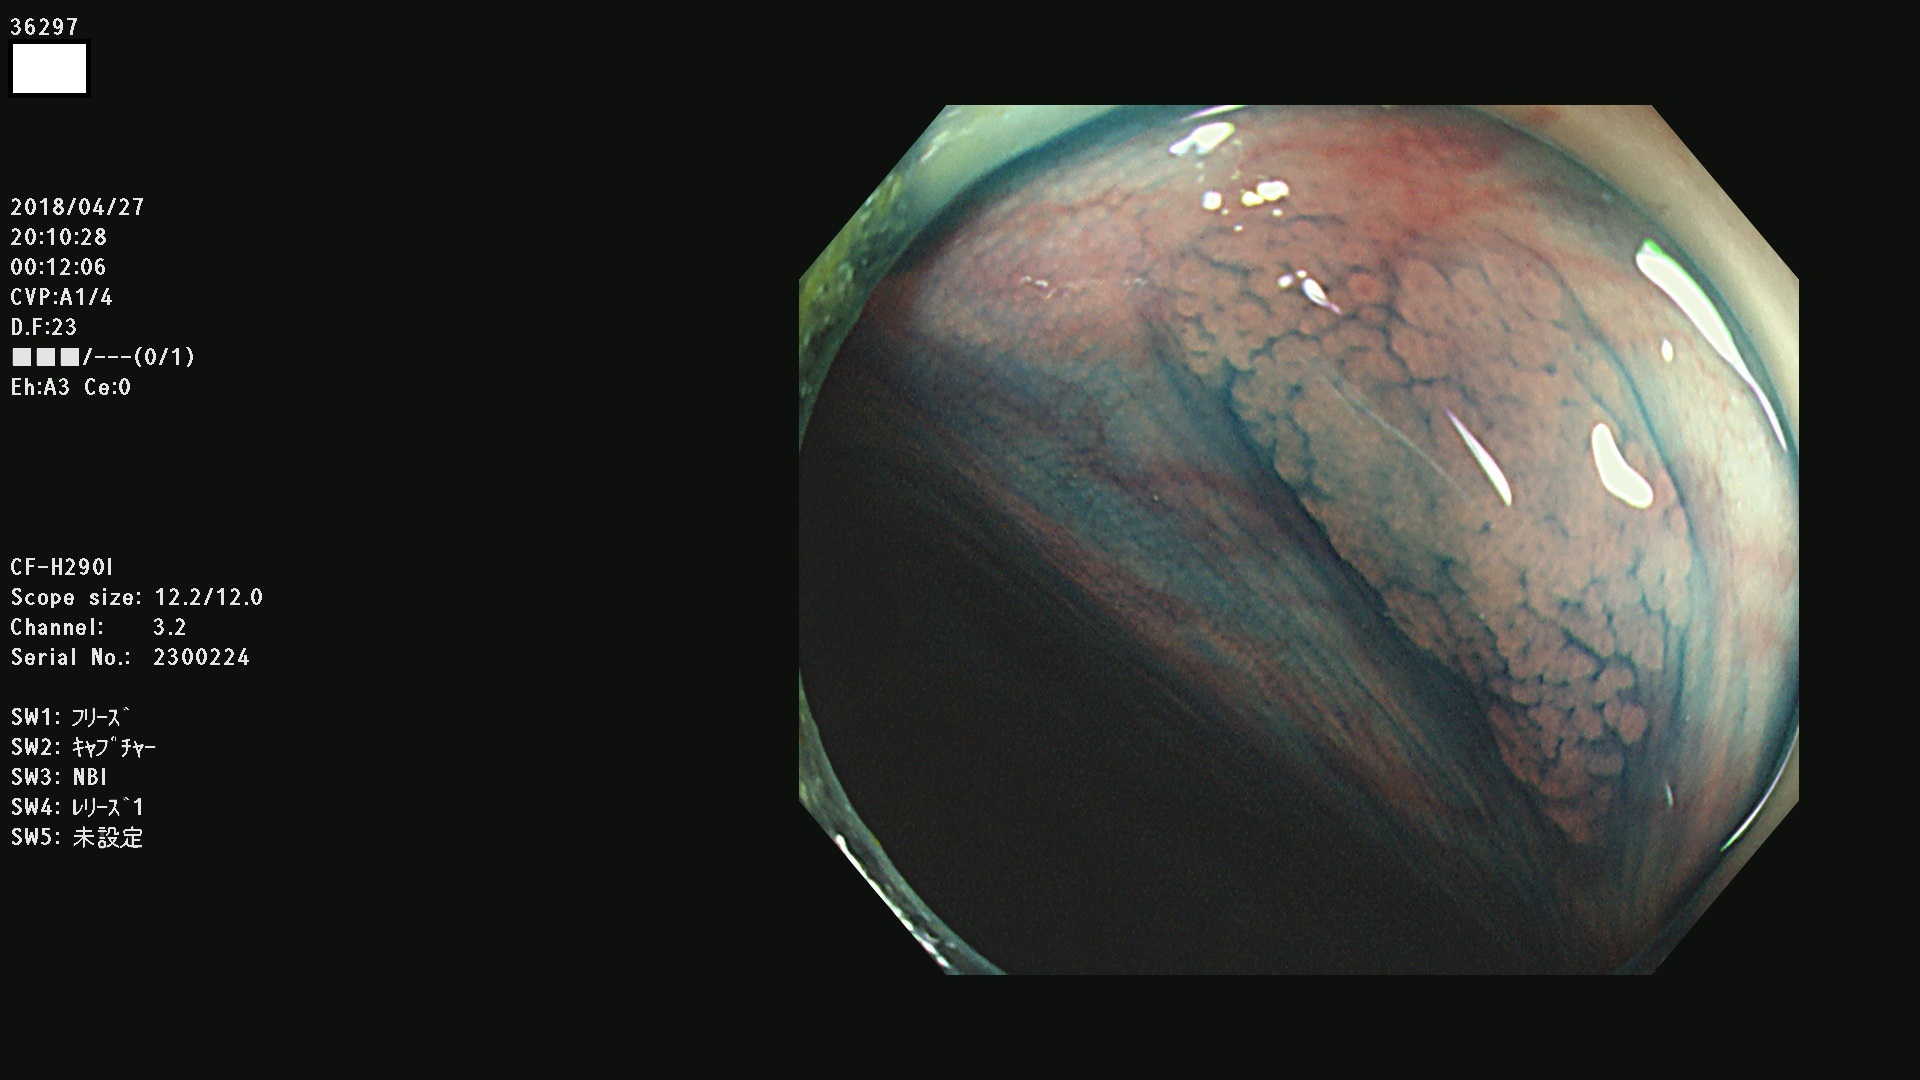

36201 36202 36203 36205 36207 36209 36210 36212 36213 36214 36215 36217 36220 36221 36222 36224 36225 36226 36227 36229 36230 36231 36232 36235 36236 36238 36240 36243 36244 36246 36247(SSAPのみ。SPS) 36248 36249 36251 36252 36253 36254 36255 36256 36257 36258 36259 36261 36262 36264 36265 36267 36269 36270 36272 36274 36275 36276 36279 36280 36281 36283 36285 36288 36289 36291 36292 36295 36296 36297 36299

発見困難で危険性の高い平坦型病変(上記100名より抽出)